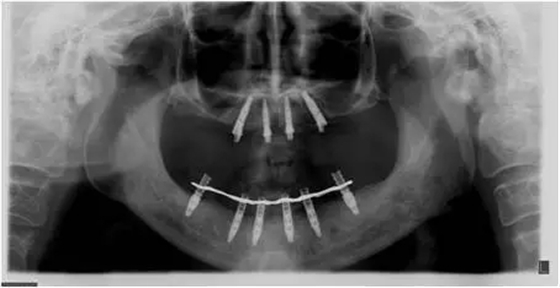

患者男性,51歲,全口無牙,下頜骨量尚可,上頜后牙區(qū)上頜竇底剩余骨高度嚴(yán)重不足,前牙區(qū)牙槽突較豐滿,主訴希望全口種植固定義齒修復(fù)。于2015年 9月接受種植治療:上頜采用All-on-4種植方案、下頜采用常規(guī)種植6顆種植體方案,種植后行即刻修復(fù)(圖1-2)。

10個月后出現(xiàn)左上頜咬合痛,X線檢查發(fā)現(xiàn)上頜左側(cè)前磨牙區(qū)傾斜種植體周圍低密度影,臨床檢查種植體松動,其余種植體骨結(jié)合良好,遂拔除該種植體(圖3-4)。愈合3個月,CBCT片顯示:25區(qū)種植窩空虛(圖5),愈合不佳,26區(qū)竇底剩余骨高度不足2mm(圖6),其余種植體骨愈合良好,15區(qū)傾斜種植體邊緣骨疑似吸收至第三螺紋(結(jié)合全景片)?;颊咭蠊潭ㄐ迯?fù)。

1、在25區(qū)補種1顆傾斜種植體,恢復(fù)ALL-on-4修復(fù)方案。造成之前種植體失敗的原因與其受力有關(guān),可能來自于修復(fù)體的咬合設(shè)計,也可能源于上、下頜種植體數(shù)量上的差異(通常上頜種植體數(shù)量應(yīng)多于下頜)。另外,放射學(xué)檢查顯示,15區(qū)種植體邊緣骨吸收較明顯,也提示存在支撐力不足的問題。后來追問病史,該患者修復(fù)后有夜磨牙情況,這進一步證實了上述判斷。鑒于此,這個方案暫不做考慮。2、增加上頜種植體數(shù)量,分別與16、25、26植入3顆,行6顆種植體支撐的常規(guī)種植固定義齒修復(fù)(圖7)。16、25、26區(qū)剩余骨高度嚴(yán)重不足是該方案的不利方面,存在因需要上頜竇底提升手術(shù)所帶來的相應(yīng)手術(shù)風(fēng)險。但是,上頜竇底提升術(shù)是一個成熟、可靠的技術(shù)方法,經(jīng)過與患者充分溝通,最終選擇了這一方案。